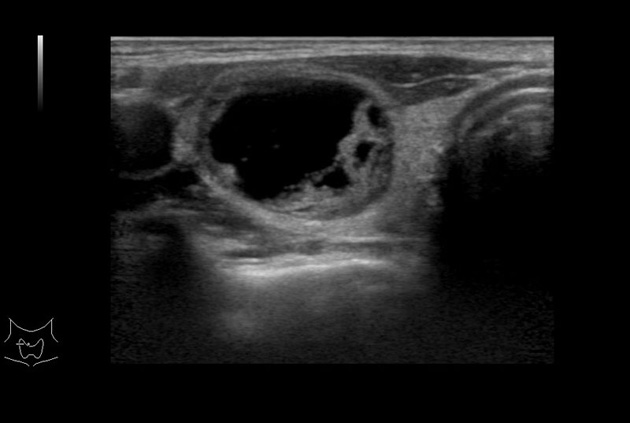

Learn moreArietta 65

The Arietta 65 has many advanced and unique probes that fully cover the expanding range of procedures that benefit from ultrasound guidance.

Learn moreArietta 65

The Arietta 65 has many advanced and unique probes that fully cover the expanding range of procedures that benefit from ultrasound guidance.